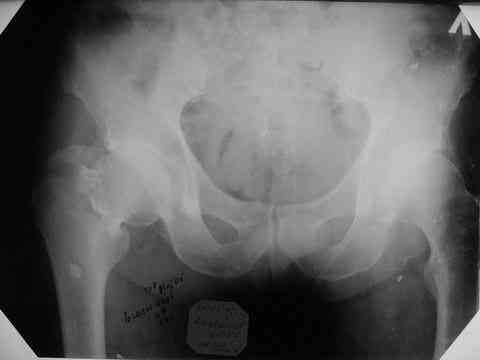

Все-таки хочу поделиться раз затронулась тема, может кому-нибудь и сгодиться. Это пример из области скорее трудноудаляемой. Пациент 50 лет, травма (низкоэнергетическая) 1,5 года назад. Оперирован через неделю (винт отечественный). Через 4 месяца выполнен контрольный снимок, сразу же возник вопрос: почему винт не телескопировался? Вопрос в общем-то так и остался без ответа.